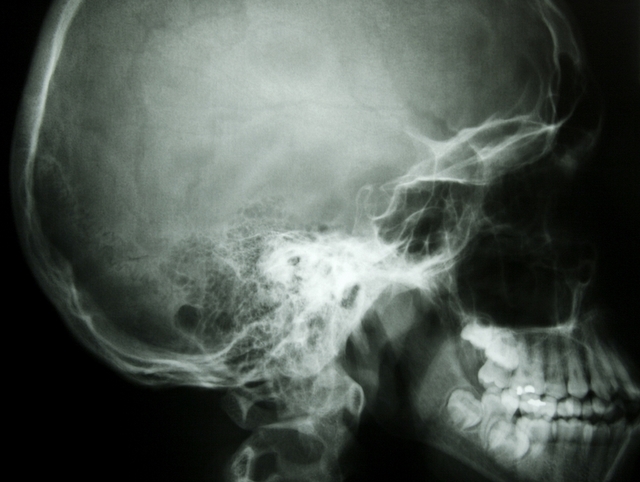

Later, if an athlete sustains a "head hit," this first test becomes a comparison tool. According to neuropsychologist Anthony Morrison, "We can tell by, comparing the post-concussion score to the baseline, if there is a significant deterioration in the performance, which may not be obvious and may not be picked up on a cat scan or an MRI."